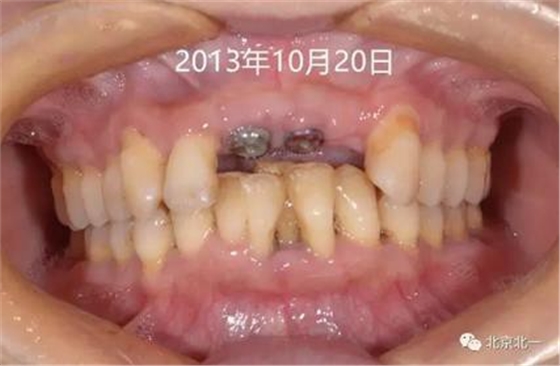

圖三:五月后二期手術(shù)

圖四:牙齦袖口,未做牙齦成形。

圖五:戴入基臺(tái),采用粘接固位。